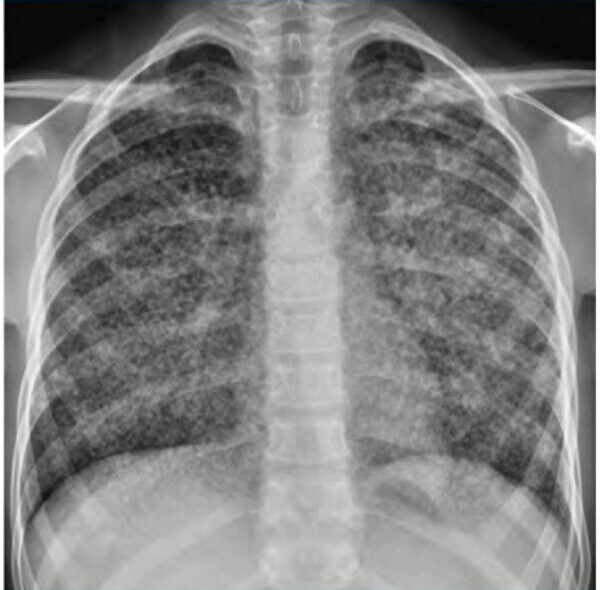

En el diagnóstico de infiltrados pulmonares en pacientes inmunocomprometidos, la radiografía de tórax suele tener una utilidad limitada para acotar el diagnóstico diferencial. Dado que la radiografía puede no ser específica ni suficiente para determinar la causa subyacente, es crucial utilizar métodos adicionales para identificar el patógeno responsable.